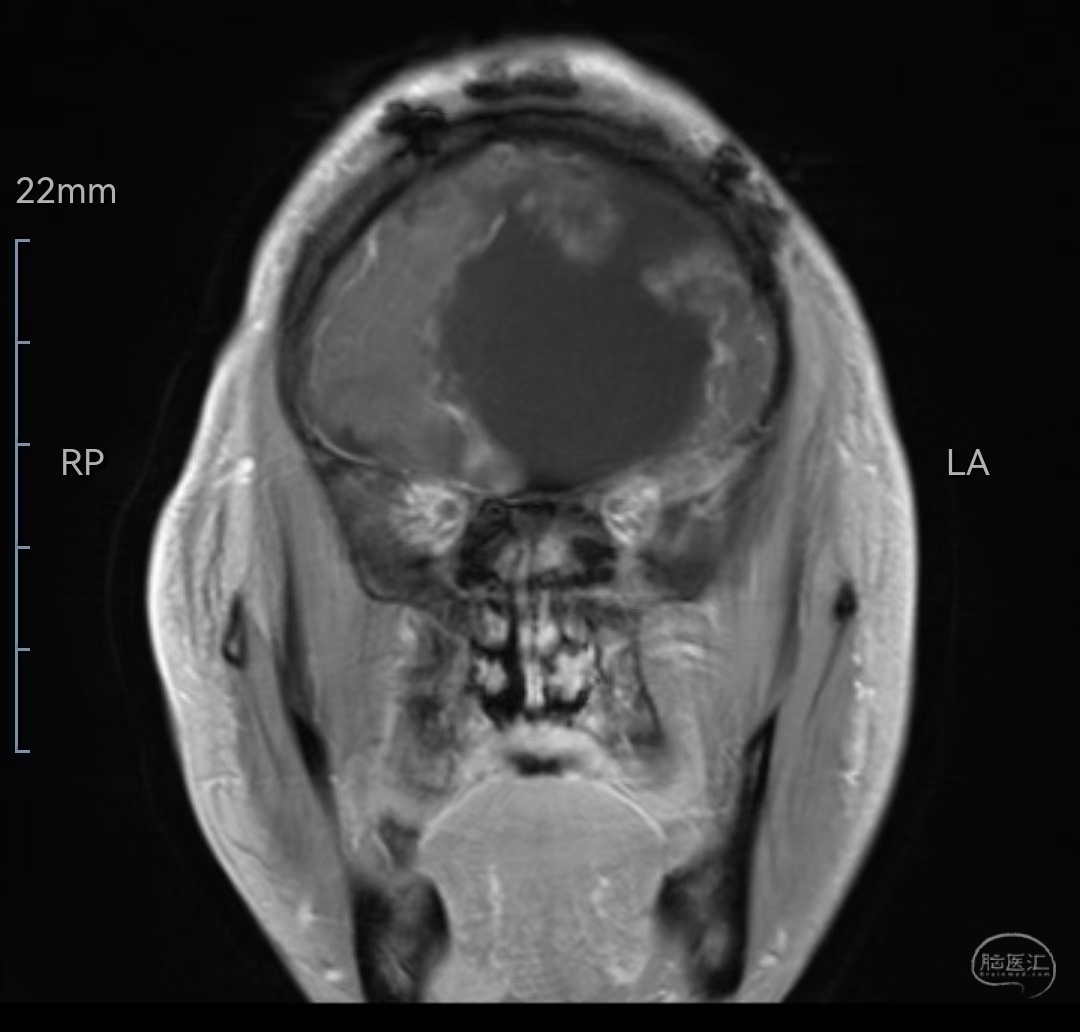

MRI增强冠状位示肿瘤明显强化,位于双侧额叶,左侧为主

MRI增强冠状位示肿瘤全切除,脑组织保护佳